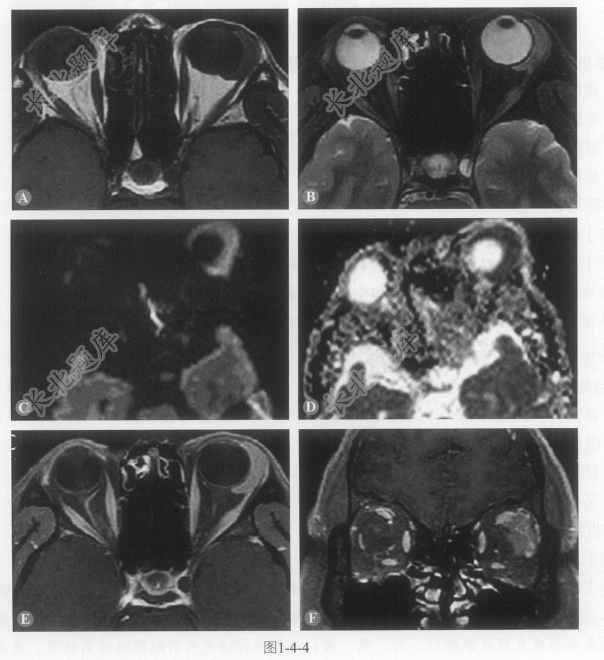

- 多项选择题1.该患者的影像学表现(图1-4-4)包括:

A、左侧泪腺区占位

B、瘤体呈铸型生长,部分包绕眼球,占位效应不明显,无明显眶壁骨质破坏

C、肿瘤信号均匀,在T

WI呈等信号,T2WI呈略高信号D、肿瘤DWI序列呈高信号,表观扩散系数(apparent diffusion coefficient,ADC)图显示扩散受限

E、肿瘤增强呈中度均匀强化